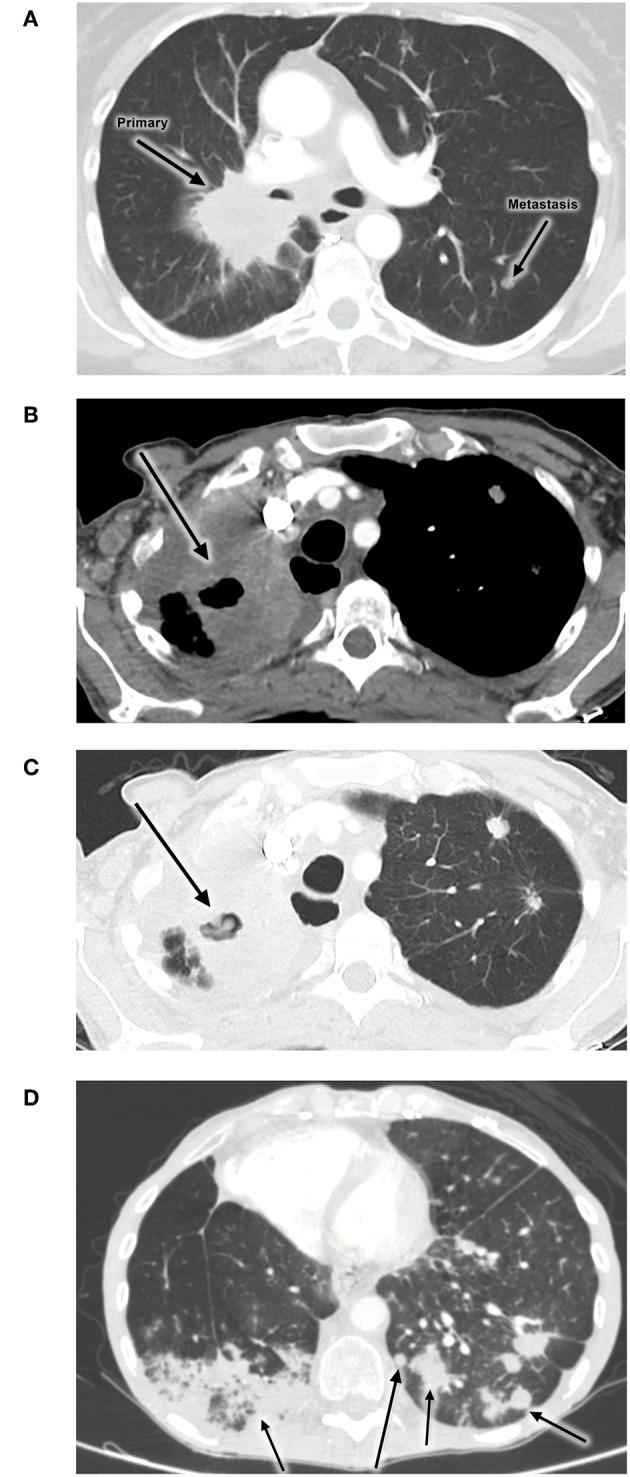

Nivolumab (PD-1 inhibitor) and other immune checkpoint inhibitors are used primarily to promote reactivation of anti-tumor immunity. However, due to their generalized immunorestorative properties, these agents may also trigger an unusual spectrum of side-effects termed immune-related adverse events. In the case of the lung, pulmonary infiltrates in patients treated with the anti-PD-1 inhibitors, nivolumab, or pembrolizumab, especially patients with non-small cell lung cancer, can result from immune-related pneumonitis, which, until fairly recently was believed to be of non-infective origin. This, in turn, may result in progression and pseudo-progression of disease. An increasing body of evidence has, however, identified pulmonary tuberculosis as an additional type of anti-PD-1 therapy-associated, immune-related adverse event, seemingly as a consequence of excessive reactivation of immune responsiveness to latent infection. The current case report describes a 56-year old Caucasian female who presented with microbiologically-confirmed tuberculosis infection while on nivolumab therapy for non-small cell lung cancer. Notably, the patient, seemingly the first described from the African Continent, had not received immunosuppressive therapy prior to the diagnosis of tuberculosis.

纳武单抗(一种PD -1抑制剂)和其他免疫检查点抑制剂主要用于促进抗肿瘤免疫的重新激活。然而,由于它们具有广泛的免疫恢复特性,这些药物也可能引发一系列不同寻常的副作用,称为免疫相关不良事件。就肺部而言,接受抗PD -1抑制剂纳武单抗或派姆单抗治疗的患者,尤其是非小细胞肺癌患者,肺部浸润可能是由免疫相关肺炎引起的,直到最近人们还认为这种肺炎是非感染性的。反过来,这可能导致疾病进展和假性进展。然而,越来越多的证据表明,肺结核是抗PD -1治疗相关的另一种免疫相关不良事件,似乎是对潜伏感染的免疫反应过度激活的结果。本病例报告描述了一名56岁的白种女性,她在接受纳武单抗治疗非小细胞肺癌时出现了微生物学确诊的结核感染。值得注意的是,该患者似乎是非洲大陆首例报告的病例,在诊断出肺结核之前未接受过免疫抑制治疗。